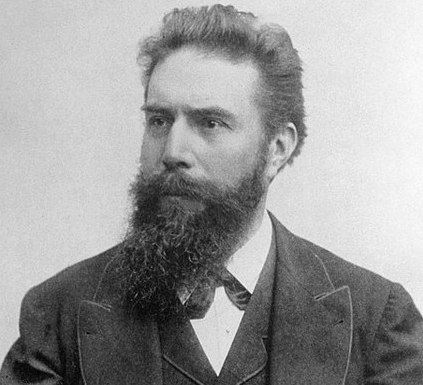

herkes wilhelm röntgen'in çekmiş olduğu, eşinin eli olan o ilk medikal görüntüden bahsetmiş, o zaman biz de tamamlayalım.

işte o fotoğraf